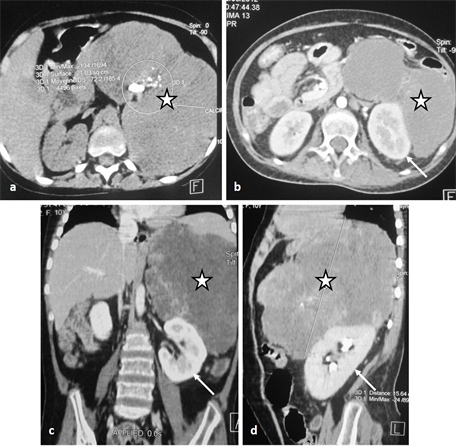

Abdominal CT-scan (Figure 4) with and without contrast agent injection showed a huge tissue mass adrenal left multilobed evaluated at 1550 cm3, punctuated by different size calcifications, raised after injection, driving the left kidney without invading it and without infiltration of the adjacent fat; there are no

Figure 4. Abdominal CT scan showing a huge tissue mass adrenal left multilobed evaluated at 1550 cm3 (stars in (a)-(d)) punctuated by different size calcifications (circle), raised after injection, driving the left kidney (arrows in (b)-(d)) without invading it and without infiltration of the adjacent fat; there are no deep lymphadenopathies. The aspect was compatible with a left adreno-cortical carcinoma.

deep lymphadenopathies. The aspect was compatible with a left AC. The rest of the exploration was normal.